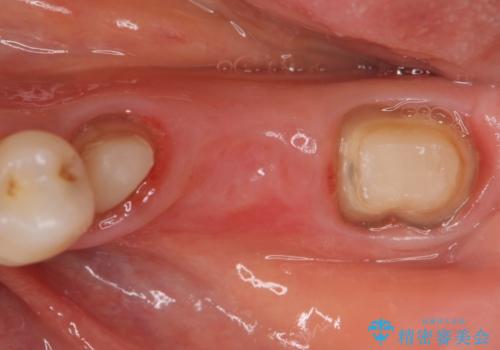

- 他院にて左下奥歯のポケットが深いと言われた、銀歯と歯茎の隙間も気になるのでまとめて治療して欲しいと来院された方の症例です。

左下7の遠心部は部分的な骨欠損によるポケットが10mmあったため、再生療法による骨の再生を行いました。